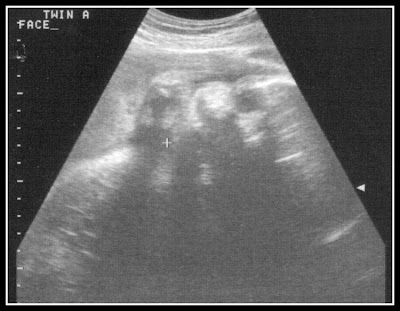

We still don't get to see Baby B's face ever, but Baby A shows us her sweet little face every ultrasound. It's a little hard to see, but this is her looking straight at us again. You can see her eye near the top and then her little nose. The best part is her little chubby cheek!!!